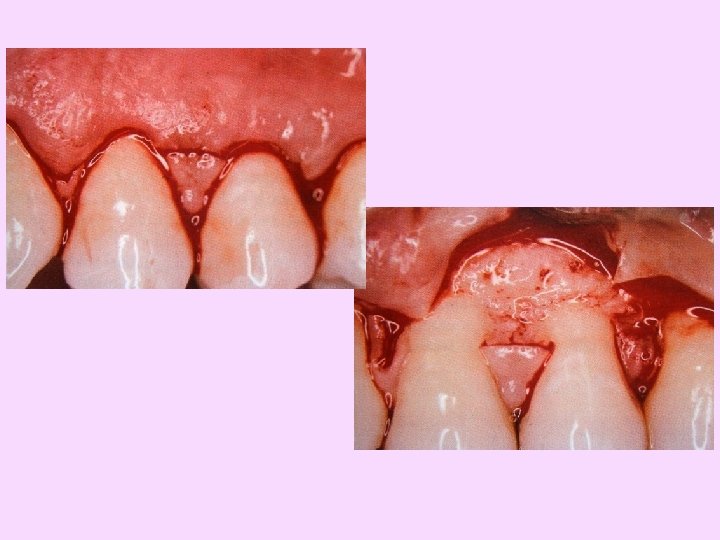

Placement of incision

Flap reflection

Debridement of the defect area

Placement of membrane